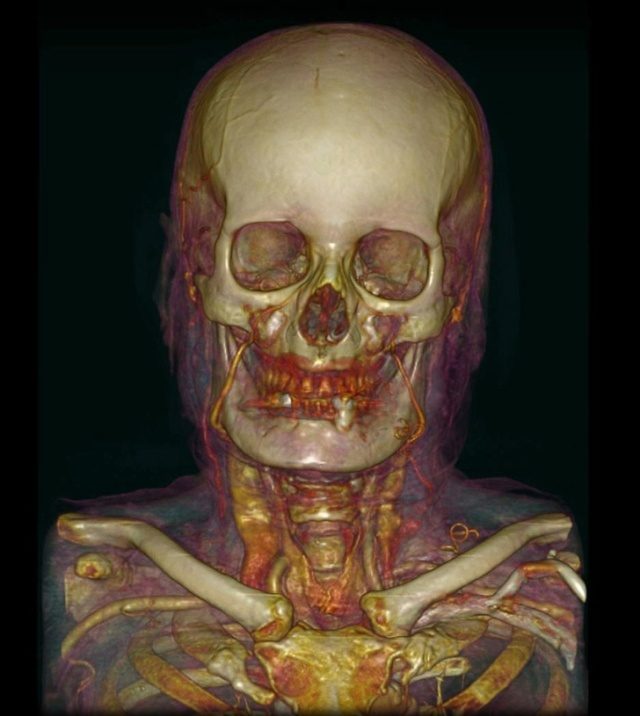

Томография сосудов и черепа